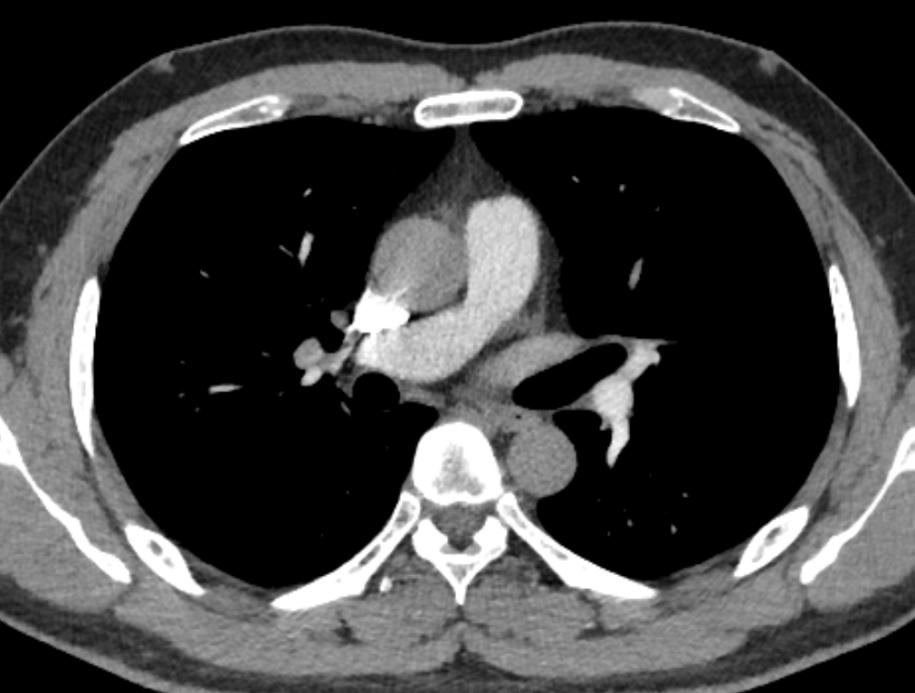

增强CT在高速团注时应优先选择血管条件好、管径粗、影像伪影少、路途短的血管快速将对比剂汇入心脏完成循环。大多数人右上肢血管管径粗、走形直,没有太多的弯曲,造影剂经头臂静脉直接进入上腔静脉的路程短且通畅。

右锁骨下静脉经头臂静脉直接进入上腔静脉

2.常规优先选择右上肢留置穿刺针: